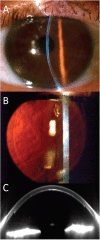

Methods: A CZM 500 kHz Visumax femto-second laser was used. Organ cultured donor grafts were mounted in an artifical anterior chamber with the endothelial side up and out. Posterior grafts of 7.8 mm diameter and 130 micron thickness were prepared by femto-second laser cutting. A standard DSAEK procedure was performed in 10 patients with Fuchs endothelial dystrophy. Patients were followed-up regularly and evaluated by measurement of complications, visual acuity, corneal thickness (Pentacam HR), and endothelial cell density.

Results: Femto-laser cutting of grafts and surgery was uncomplicated. Rebubbling was necessary in 5 of 10 cases (normally only in 1 of 20 cases). All grafts were attached and cleared up during the first few weeks. After six months, the average visual acuity was 0.30 (range: 0.16 to 0.50), corneal thickness was 0.58 mm (range 0.51 to 0.63), and endothelial cell density was 1.570 per sq. mm (range: 1.400 to 2.000 cells per sq. mm). The grafts were of uniform thickness, but substantial interface haze was present in most grafts.

Conclusions: Posterior lamellar corneal grafts can be prepared from the endothelial side using a femto-second laser. All grafts were clear after 6 months with satisfying endothelial cell counts. Poor visual acuity caused by interface scatter was observed in most patients. Femto-second laser cutting parameters needs to be optimised to enable smooth cutting in the posterior stroma.